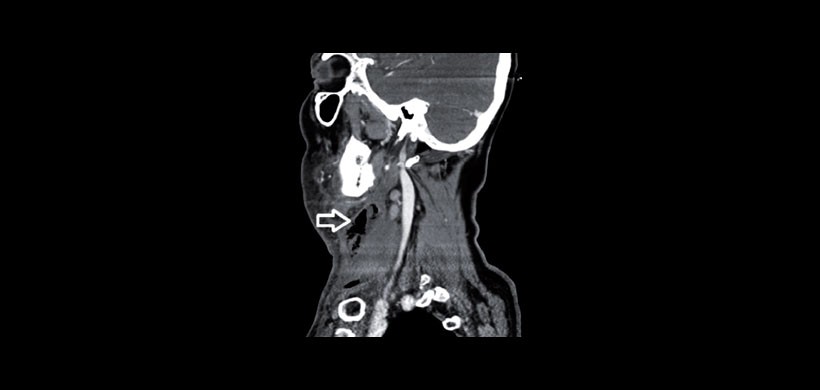

Paciente masculino de 66 años con quejas de fiebre, hinchazón en el cuello, enrojecimiento y falta de aliento. No se conoció diabetes o inmunodeficiencia en este caso. Al examen físico reveló una inflamación media que fue aproximadamente 10 cm de dimensión y era más grande de lado derecho del cuello. En el examen de laringoscopio las cuerdas vocales eran edematosas y tenían movimiento normal. La tomografía computarizada de cuello (CT) mostró sialoadenitis submandibular derecha y absceso inducida por un cálculo intraductal. (Figuras 1-3).

Como conclusión se llego al diagnóstico de Fascitis Necrotizante cervical, siendo la base del diagnóstico el estudio imagenológico que en esta ocasión se usó la Tomografía Computarizada.